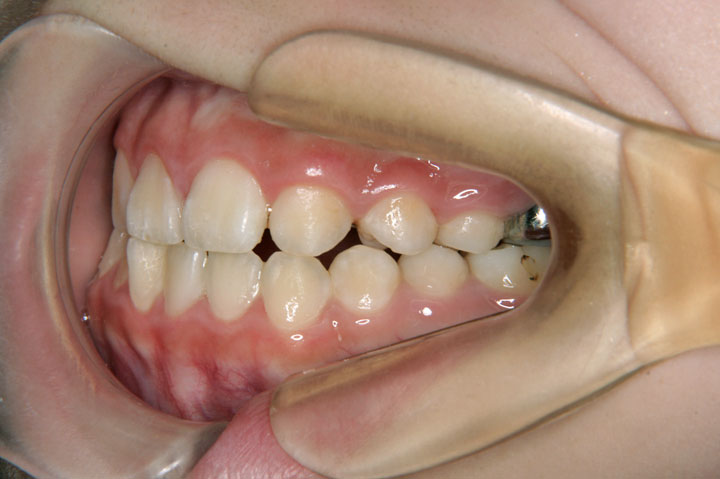

口唇口蓋裂患児のため、関連病院からの紹介で当院を受診されました。小学校4年生の女子です。口蓋裂のため上顎の側方への成長が悪く、拡大床、クォードヘリックスを用い、側方拡大を行いました。その後、永久歯列への交換を待って、エッジワイズ治療を行っております。また、上顎側切歯が両側とも欠損でしたが、大きな違和感もなく配列することができました。